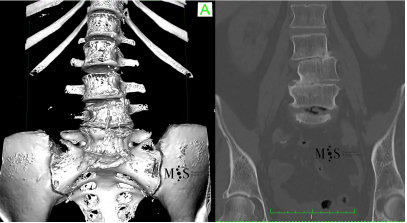

Imagen de una escoliosis degenerativa. Obsérvese el desplazamiento y la asimetría

de las vértebras en la zona lumbar y el disco negro en L5/S1 (implica inestabilidad).